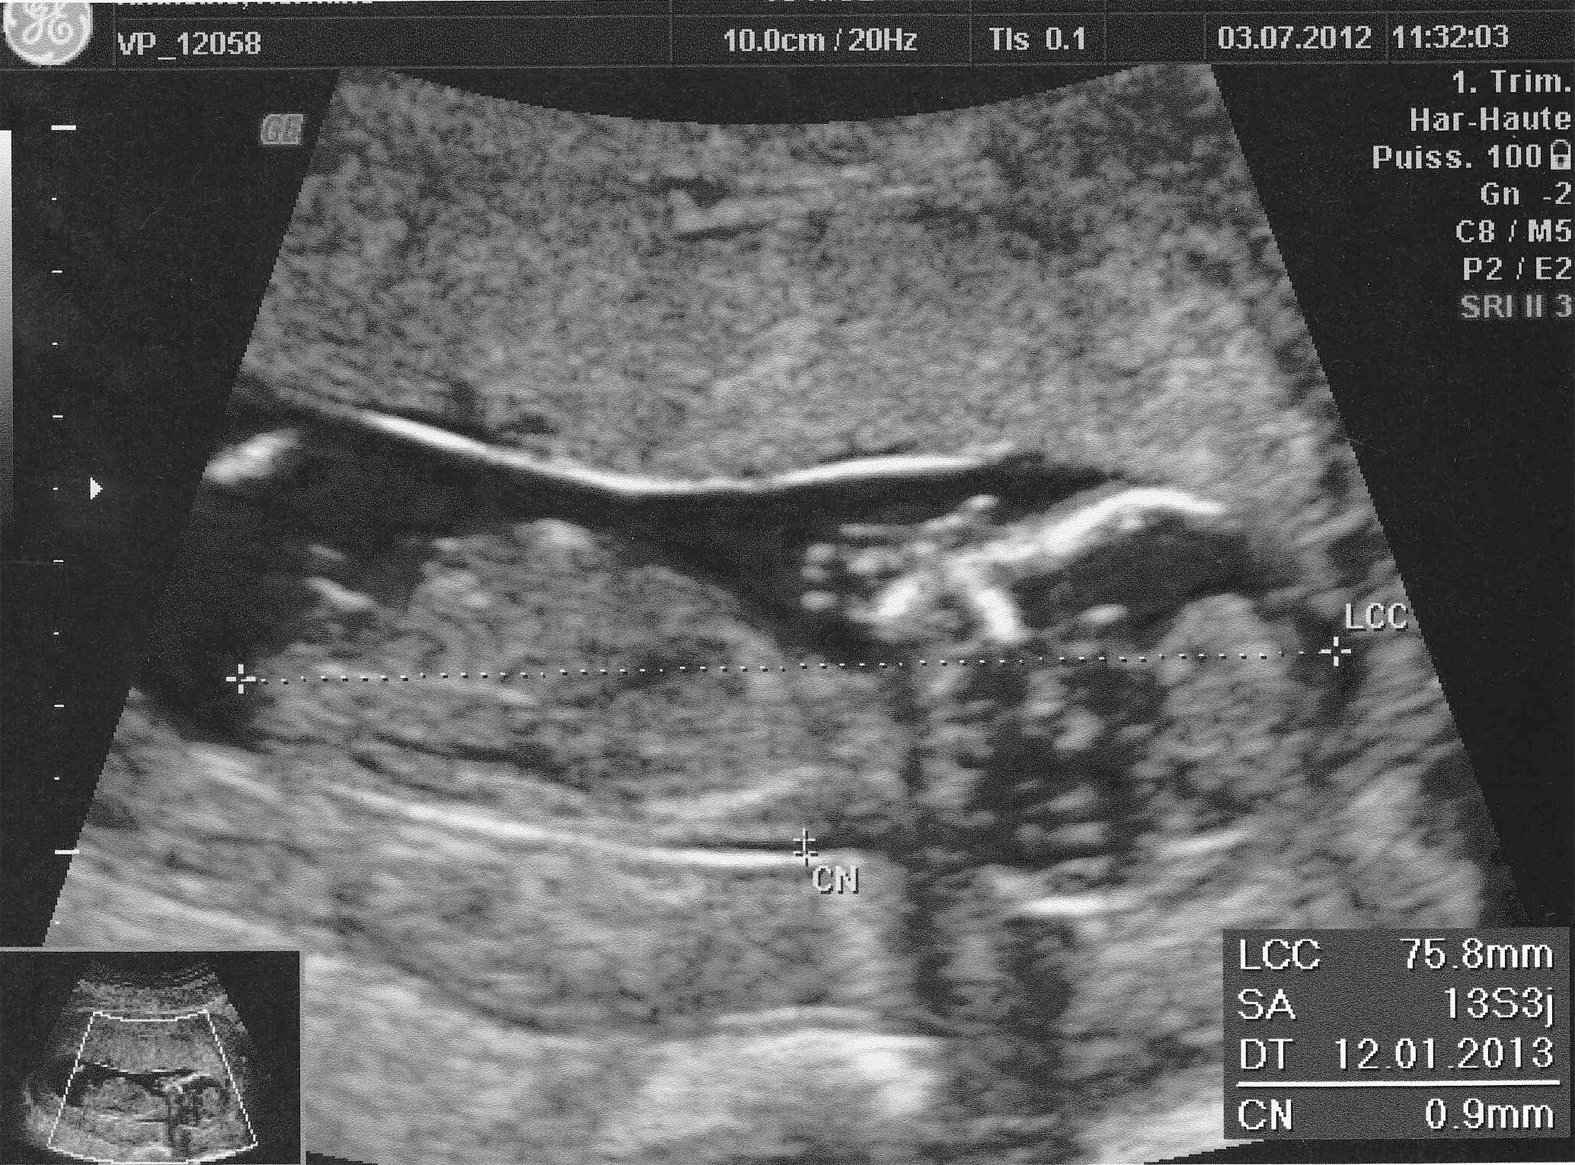

La naissance d’un enfant est bouleversante. Rien, même les images échographiques les plus évoluées, aucune photo ou film n’est à la hauteur de cette rencontre tant attendue avec l’enfant que l’on tient enfin dans nos mains. Entre la représentation de l’enfant que l’on a rêvé presque 9 mois, les récits des copines et même ceux de notre maman, cette rencontre est définitivement unique et restera suspendue dans nos souvenirs: cet instant est sinon le meilleur, le plus grand de notre vie de parent.